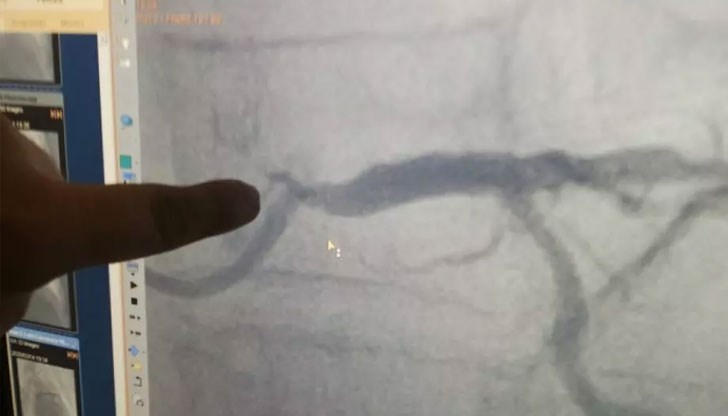

Инфарктът бил на дясната коронарна артерия, но по правило трябвало да проверят и вляво, от където се кръвоснабдяват много повече съдове, отколкото отдясно.

„Когато проверихме отляво, се оказа тотална катастрофа - над 90% стеснение на ствола, което практически е почти несъвместимо с живота. Дясната артерия на 100% запушена с остър инфаркт, а вляво 90%. И всичко това на тази жена, която външно няма никакви белези за толкова тежко увреждане. Освен това тежко запушване, самите кръвоносни съдове бяха изключително калцирани“, допълва д-р Илиев.